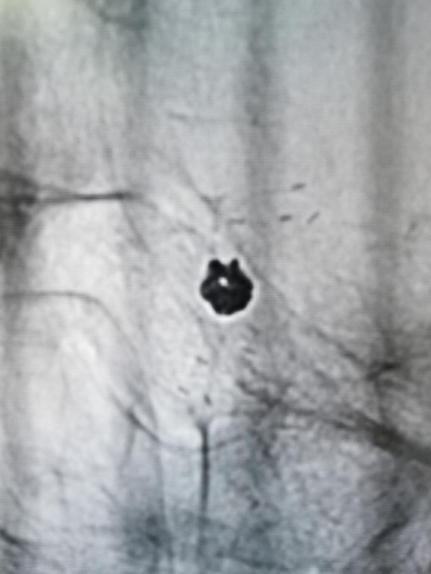

4.入路血管损伤

手术材料:

术中栓塞:

此患者颈内—眼动脉瘤为宽颈动脉瘤,单纯弹簧圈栓塞有导致弹簧圈脱出或者栓塞不致密复发率高的可能,支架弹簧圈辅助栓塞是目前较为主流的介入治疗方式,Enterprise2支架是自膨式激光雕刻闭环支架,操作简单,精准定位,输送性佳,容易通过迂曲病变。

Enterprise2支架同1代支架相比,通过增加支架直径和正弦波几何结构的波幅,改善支架在弯曲血管中的贴壁性,在弯曲血管大弯侧避免支架丝突入瘤腔,更安全;在弯曲血管小弯侧无“鱼嘴效应”,致密栓塞率更高,同时增加了支架标记的可视性。